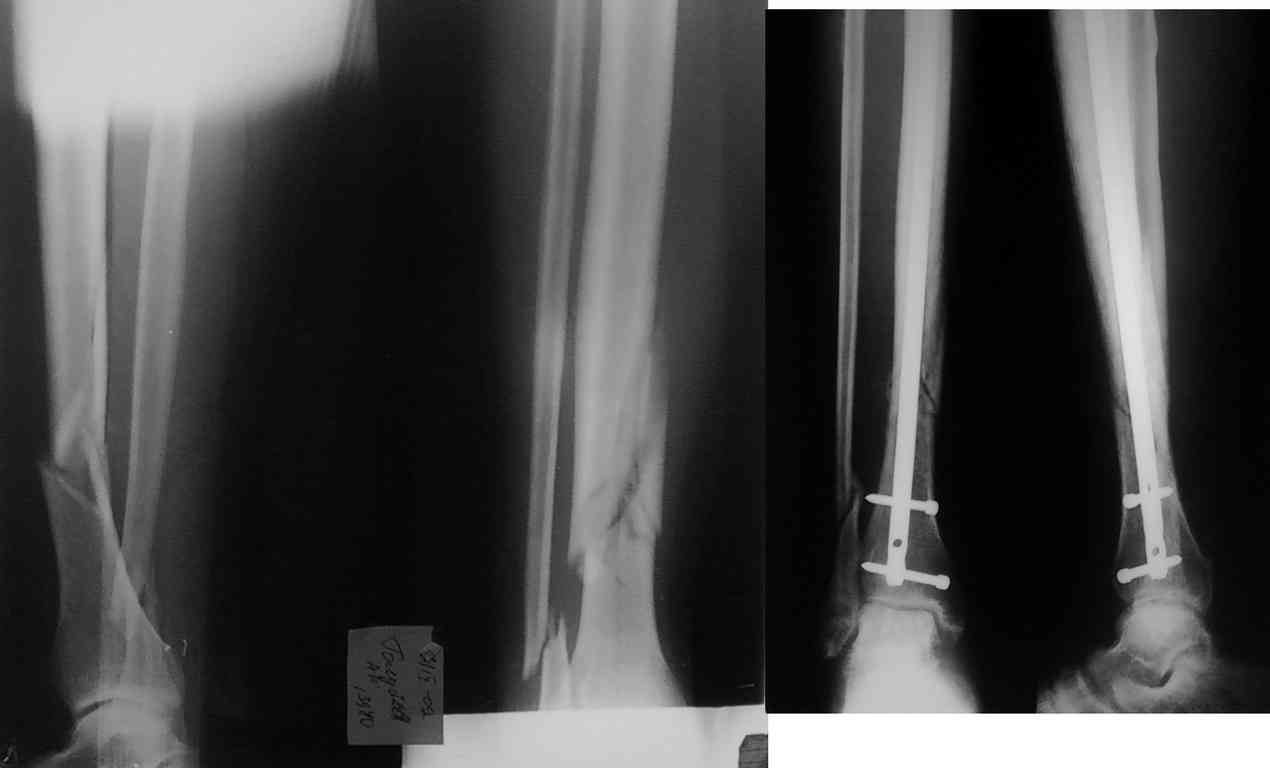

Пациент Г. 40 лет. 7 сентября 2009 госпитализирован в травматологическое отделение, через 1 час после производственной травмы с диагнозом: закрытый неосложненный оскольчатый перелом правой голени в с-н/3. 23 сентября выполнен БИОС правой б/б кости польским стержнем. Задержка в операции обусловленна высокой температурой в первые 10 дней, затем на узи - тромбоз сурального синуса справа и после консультации сосудистого хирурга и антикоагуляционной терапии выполнена операция. Выписан на 10 сутки с рекомендацией ходить с дозированной нагрузкой. Пациент результатом доволен.

Вопрос по тактике лечения. В данном случае есть перелом м/б кости над синдесмозом, по-моему с небольшим укорочением. Я бы в этой ситуации выполнил еще и МОС перелома м/б кости.

При диафизарном переломе малоберцовой в этом практически никогда нет необходимости. При остеосинтезе в свежем случае восстанавливается длина обеих костей.